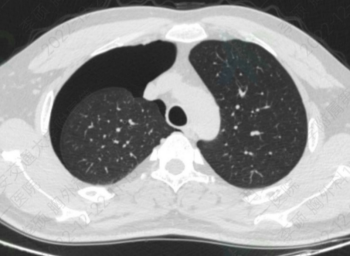

新冠患者咳嗽后出现右侧气胸

前日胸外科收治了一位36岁青年男性和一位55岁中年女性。两位患者均为新冠阳性患者,在居家过程中咳嗽及体位改变后出现胸痛、气短症状前来就诊。经由急诊科分诊,根据典型症状、查体结合胸部CT诊断为气胸,诊断后行闭式引流术,治疗后胸闷气短症状明显缓解,呼吸轻快有力,预后良好。